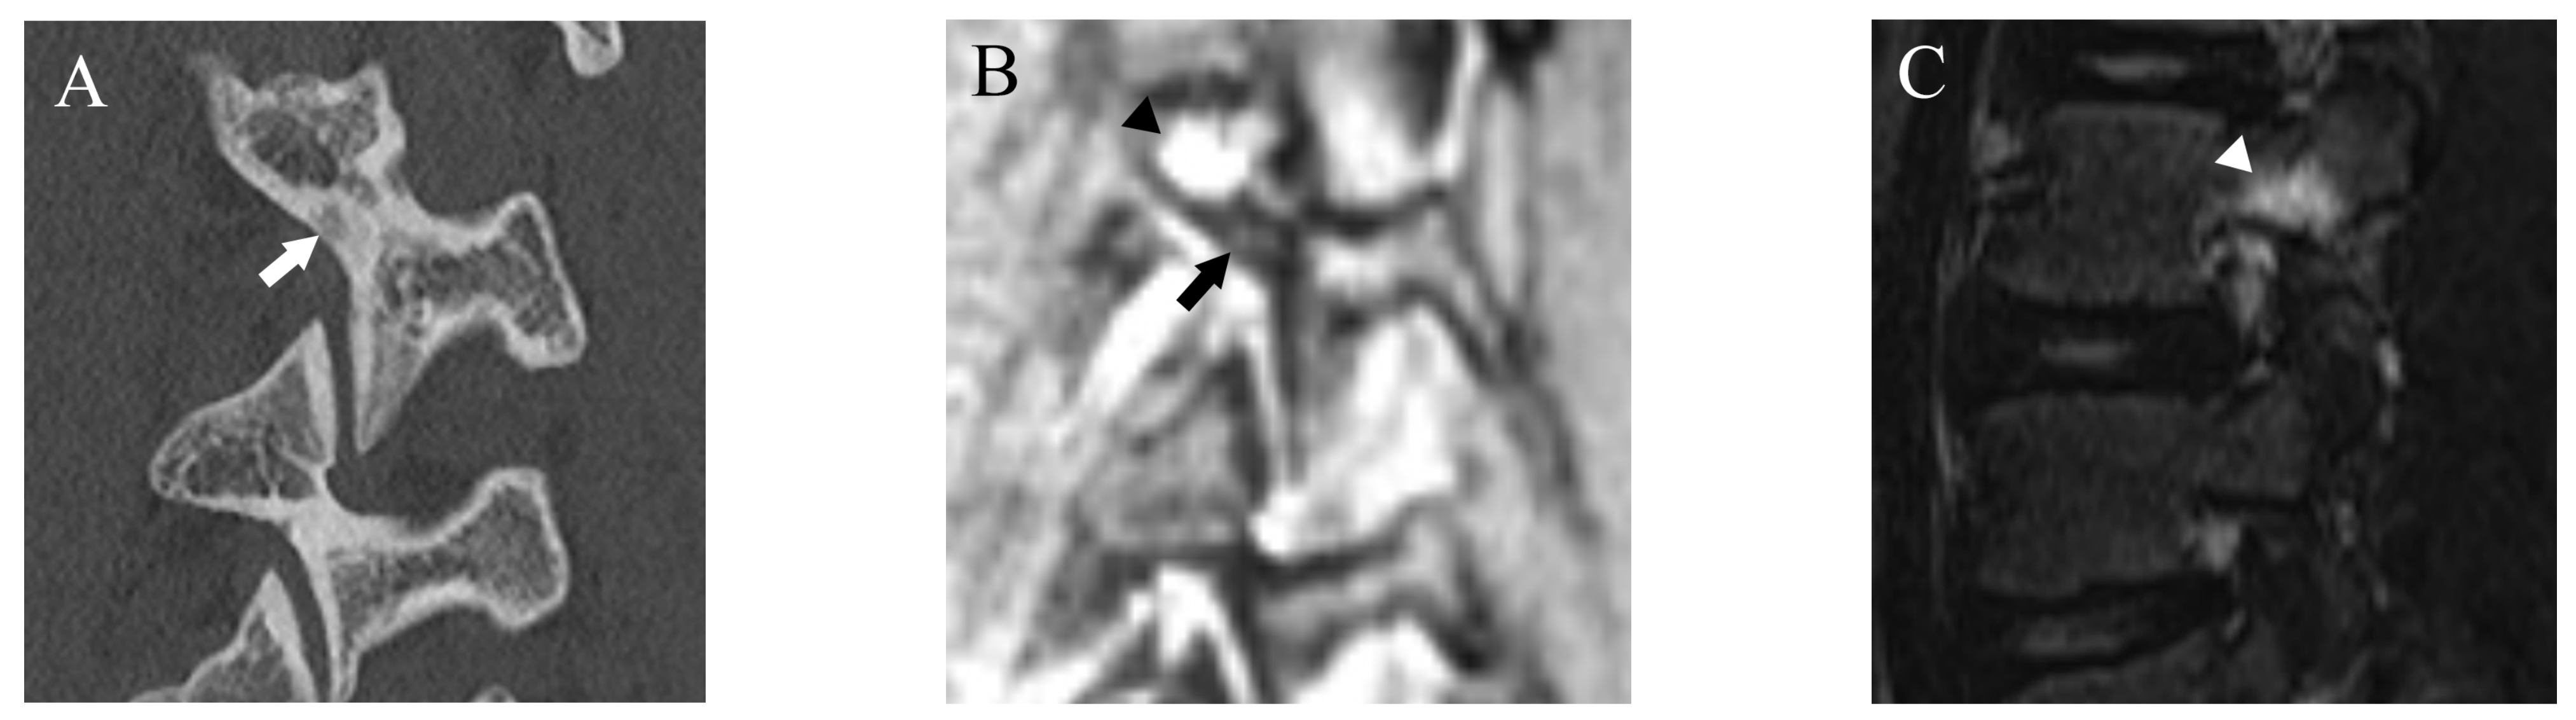

Figure 5.

Comparison of bilateral grade 3 fractures at L5 from an 11-year-old male in multiple planes between CT and DESS. (A–C) CT shows complete fractures in L5 pars interarticularis on the right-sided sagittal, axial, and coronal plane, respectively (arrows). (D–F) DESS shows comparable complete fracture on the right-sided sagittal, axial, and coronal plane, respectively (arrows).

Figure 6.

Comparison of grade 2 fracture at the right pars interarticularis at L5 from a 14-year-old male in multiple planes between CT and DESS. (A–C) CT shows grade 2 fracture on the right pars interarticularis on the right-sided sagittal, axial, and coronal plane, respectively (arrows). On the axial plane, fracture of the left side is also delineated (thin arrow). (D–F) DESS shows grade 2 fractures comparable to CT on the right-sided sagittal, axial, and coronal plane, respectively (arrows). The sagittal and axial images delineate BME around the fracture (arrowhead), and the left pars interarticularis fracture is also delineated on the axial image (thin arrow).